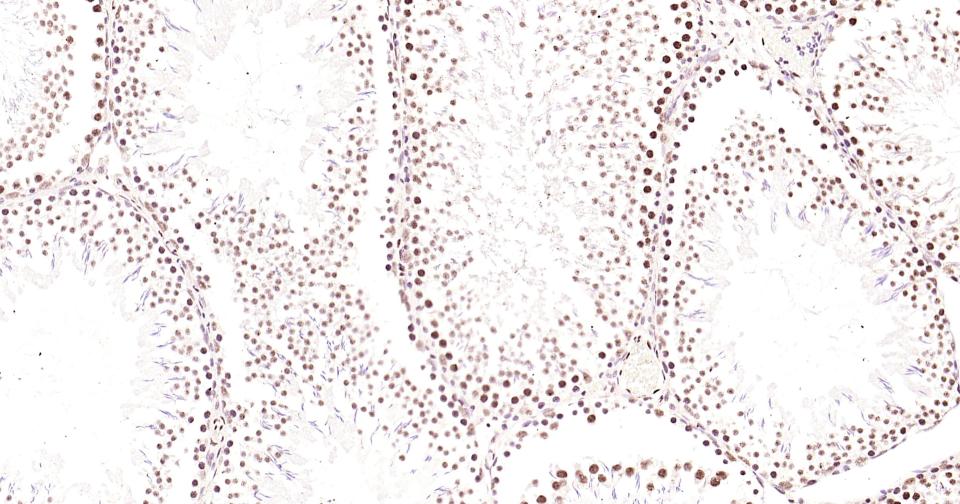

Paraformaldehyde-fixed, paraffin embedded Rat Testicles; Antigen retrieval by boiling in sodium citrate buffer (pH6.0) for 15 min; Antibody incubation with Phospho-CREB-1 (Ser133) Monoclonal Antibody, Unconjugated(bsm-61105R) at 1:200 overnight at 4°C, followed by conjugation to the bs-0295G-HRP and DAB (C-0010) staining and DAB (C-0010) staining.